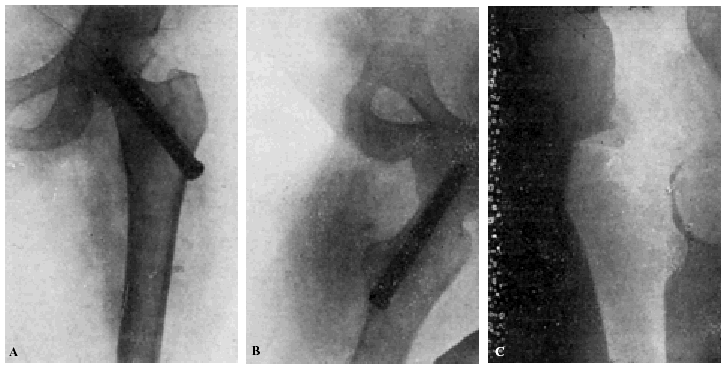

Figura 3. A: obs. núm. 2. El clavo no penetra suficientemente y la impactación, salvo en la parte superior de la línea de fractura, es muy defectuosa. B: obs. núm. 2. La posición del clavo es buena. C: obs. núm. 2. El clavo tiende a ser expulsado hacia fuera y apenas penetra en la cabeza femoral.

A los veinte días de la intervención pasa el enfermo a su domicilio, recomendándole que continúe en la cama. Pasado un mes vemos nuevamente al enfermo, el cual nos manifiesta que anda con mucha más dificultad que en los primeros días de permanecer en su domicilio, que fue cuando, por no haber interpretado bien nuestras indicaciones, comenzó a emprender la marcha. La radiografía (fig. 3. C) demuestra que el clavo apenas penetra en la cabeza femoral. A los ocho días hacemos otra radiografía (fig. 4. A), observándose que el trocáncer ha ascendido, a pesar de continuar guardando cama el enfermo. Ingresa nuevamente en el servicio, donde, con anestesia raquídea, retiramos el clavo, reduciendo las fracturas y volviendo a colocar un clavo más largo en buena dirección (fig. 4. B). Una radiografía practicada siete años y medio más tarde demuestra la no consolidación de la fractura, trastornos tróficos en cuello y cabeza femoral y que el cabo ha penetrado en el fondo de la cavidad cotiloidea, en donde ha labrado una cavidad (fig. 4. C).

Figura 4. A: obs. núm. 2. El trocánter ha ascendido francamente con relación a la radiografía anterior. El clavo tiende a salir de la cabeza por su parte superior. B: obs. núm. 2. Se extrajo el clavo y se colocó otro. El nuevo clavo está colocado en buena dirección, pero la reducción no es perfecta. C: obs. núm. 2. El clavo ha penetrado en el fondo de la cavidad cotiloidea, en cuyo lugar ha labrado una cavidad. Trastornos tróficos en cuello ycabeza femoral. El cuello del fémur ha desaparecido casi completamente.

En este caso el fracaso se debe a que la impactación no fue perfecta, y sobre todo, a haber el enfermo iniciado la deambulación al mes de intervenido, a pesar de que nosotros le ordenamos que guardara cama.